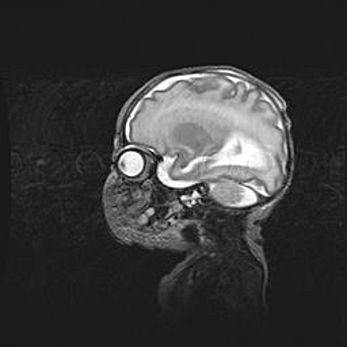

Мальформация Денди-Уокера. Киста задней черепной ямки.

Агенезия мозолистого тела.

Возраст: 2,5 месяца

Вес: 2420 г

Пол: женский

Окружность головы: 37 см

Срок гестации: 32 недели

Мальформация Денди—Уокера — редкий вид патологии ЦНС, представляющий собой врожденный порок развития каудального отдела ствола и червя мозжечка, ведущий к неполному раскрытию срединной (Мажанди) и латеральных (Лушка) апертур IV желудочка мозга. Для этогно синдрома характерна триада симптомов: гипотрофия червя мозжечка и/или полушарий мозжечка, кисты задней черепной ямки, гидроцефалия различной степени. В 70% случаев порок сочетается и с другими аномалиями головного мозга, в частности с агенезией мозолистого тела.